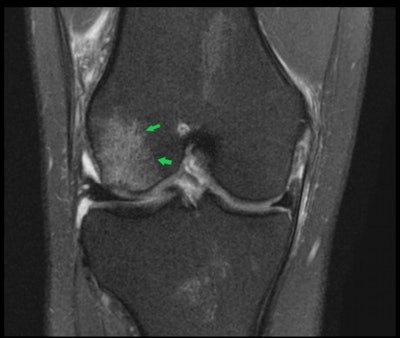

By using a Canon Medical Vantage Galan 3-tesla MRI scanner, we can see the extent of commonly occurring or unique injury onsite within the dedicated Medical Imaging Centre at the Manchester United Carrington Training Centre without any of the confidentiality issues of transferring a patient to a local hospital.

The figure below, for example, shows a T2-weighted image of the coronal view of the right knee. The female athlete has an acute pivot-shift injury with an acute lateral condylar bone contusion, which is highly indicative of an associated ACL tear.

The known predisposition in female footballers has no singular cause, but it is thought to be a mixture of anatomical differences, including the intercondylar notch, a groove at the bottom of the femur where it meets the knee, which is larger in men than in women; increased knee valgus, the Q angle formed between the quadricep muscles and the patella tendon; hip-width differences affecting knee alignment; gender biomechanics, such as joint flexibility, hormones, and menstrual cycles; plus potentially gender differences in early football training.